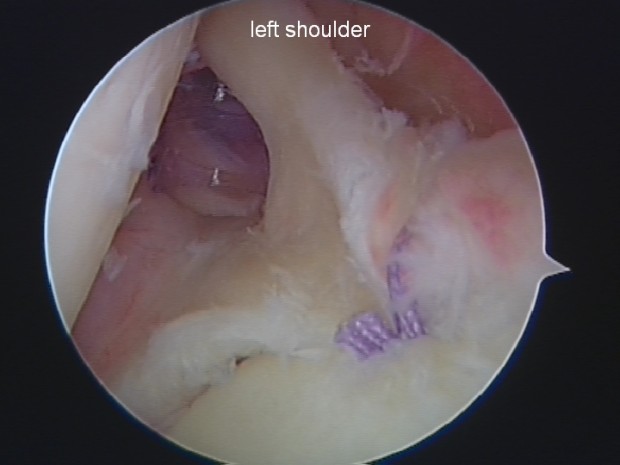

This is the SLAP tear, left hand side of the pic is Dan’s humeral head – and you can see the SLAP has already ‘folded over’ on itself as the Bankarts repair has already been carried out. At the top of the picture you can just see the biceps tendon.

Humeral head on the left and the thick tendon coming from the top of the pic is the biceps tendon. The SLAP has been repaired – and it was extremely tricky to do so due to putting the anchors to the right of the biceps tendon as you look at it. To the left of the biceps tendon you can see the clear tube which the instruments travel down to carry out the repair.